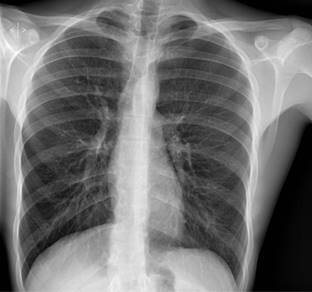

A la exploración física (EF) se encuentra con constantes vitales dentro de la normalidad, con buena saturación. Se destaca hipofonesis en región anterior de ápex pulmonar izquierdo, por lo que se realiza una radiografía de tórax en la que se aprecia un neumotórax izquierdo del 15% (Figura 1) según el índice de Light. El electrocardiograma y exámenes de laboratorio fueron normales.

Figura 1: Rx tórax postero-anterior en bipedestación: neumotórax pequeño izquierdo de 15% según el índice de Light, que no condiciona desplazamiento mediastínico.